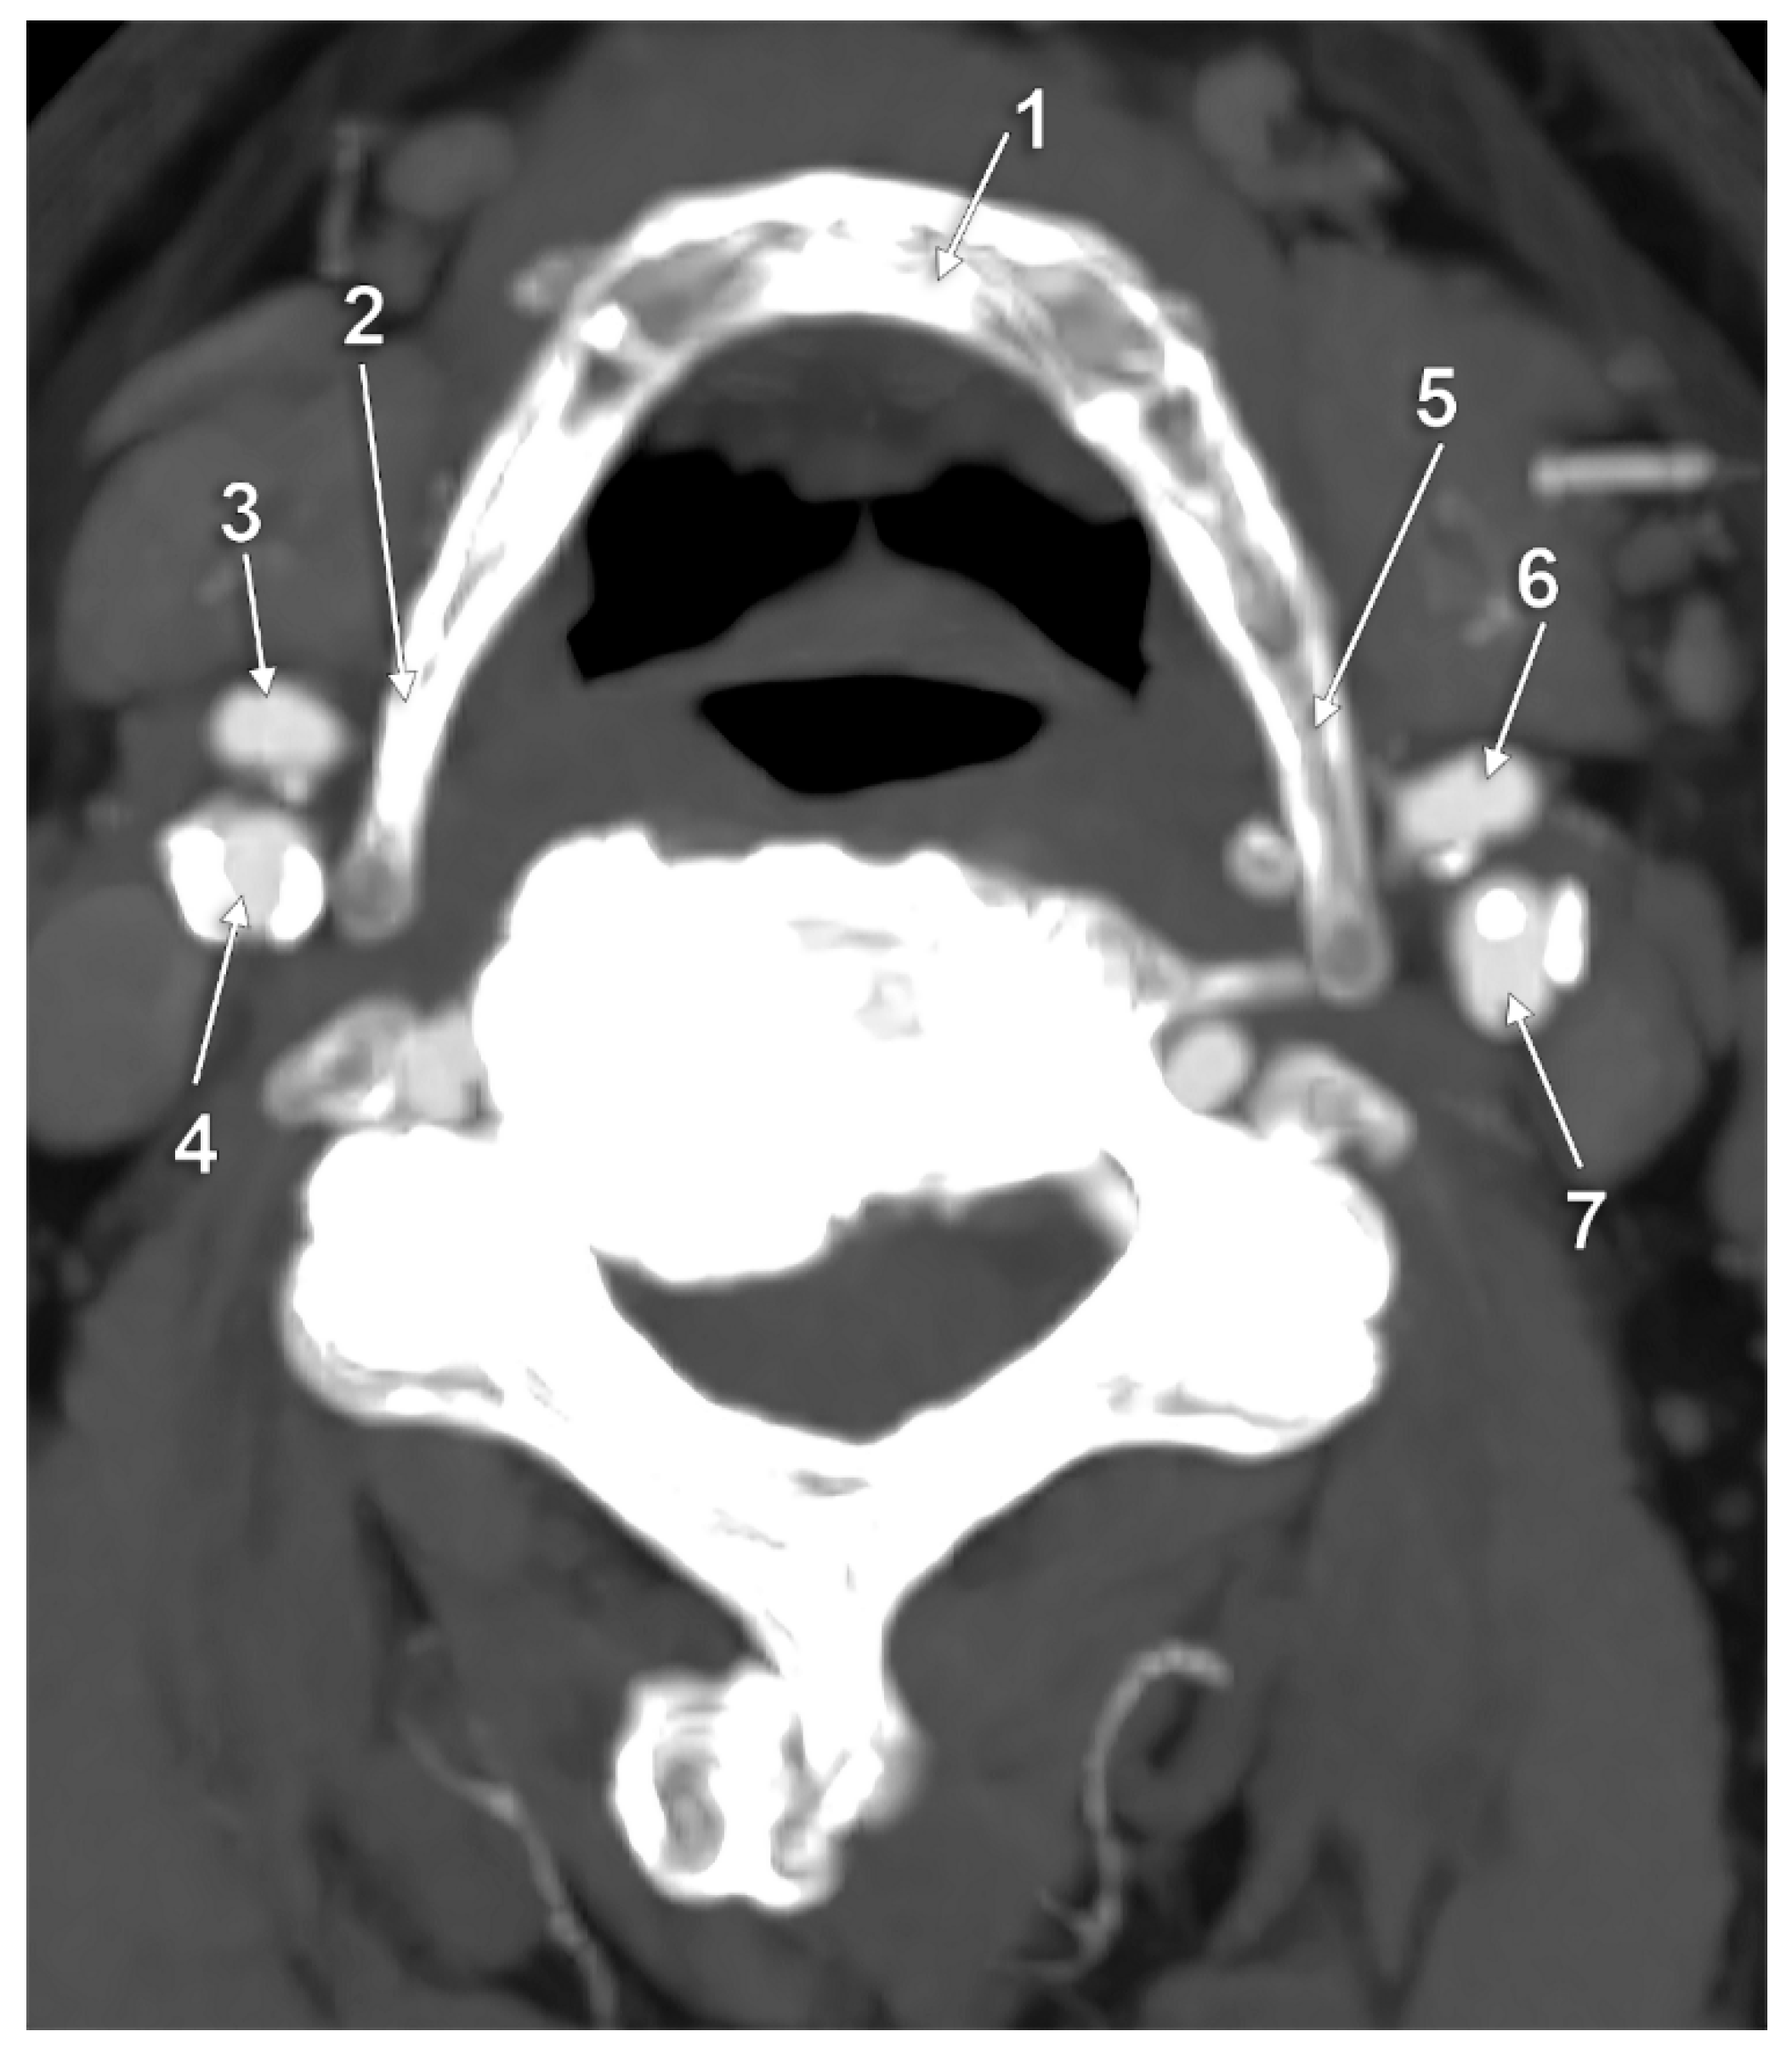

3. Results